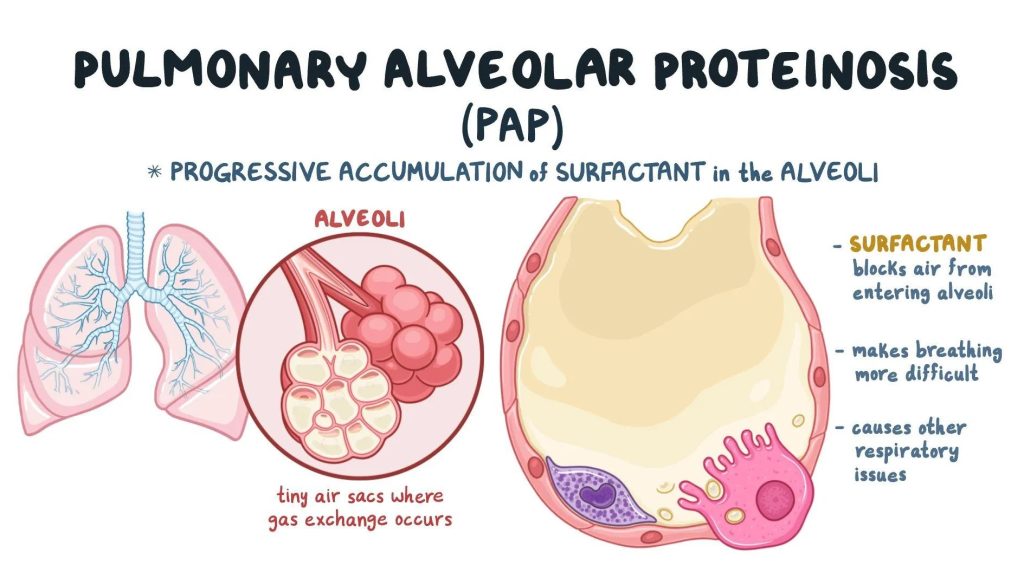

What is Alveolar Proteinosis?

Alveolar Proteinosis (AP) is a rare lung disease characterized by the buildup of surfactant (a fatty, protein-rich substance) in the air sacs (alveoli) of the lungs. This accumulation prevents proper oxygen exchange, leading to breathing difficulties and other complications. The condition can occur in different forms, including autoimmune, congenital, and secondary alveolar proteinosis.

1. Chest X-ray or CT Scan?

- Shows “crazy paving” pattern, indicating lung abnormalities.